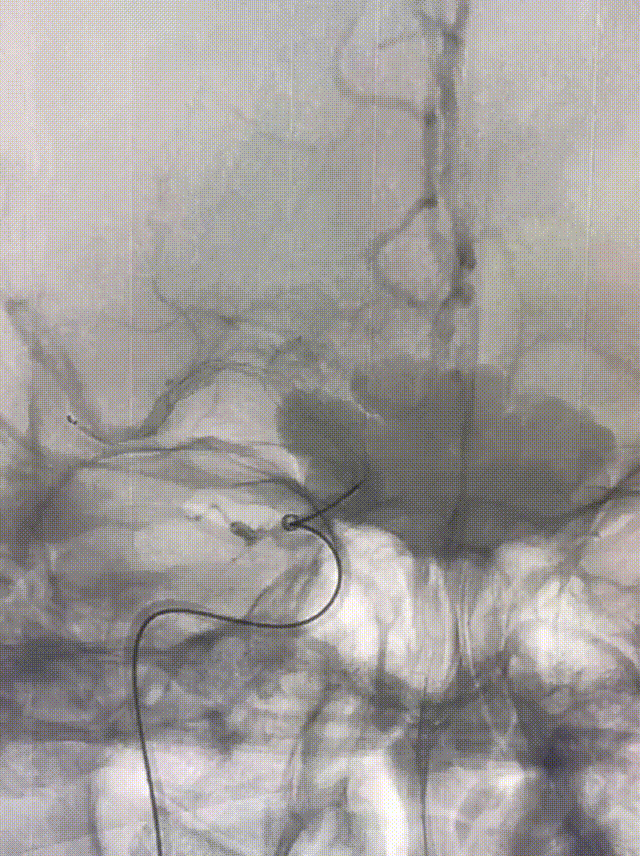

NeuroHawk Case 9